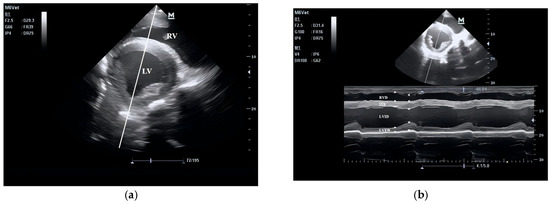

2.3. Echocardiography and Blood Sample Collection

3.1. Echocardiographic Parameters of Horses